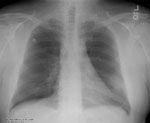

The patient is an elderly man with a history of lymphoma that presents with fever, cough, and an elevated white blood cell count.

The initial chest radiograph demonstrated a left lower lobe infiltrate.